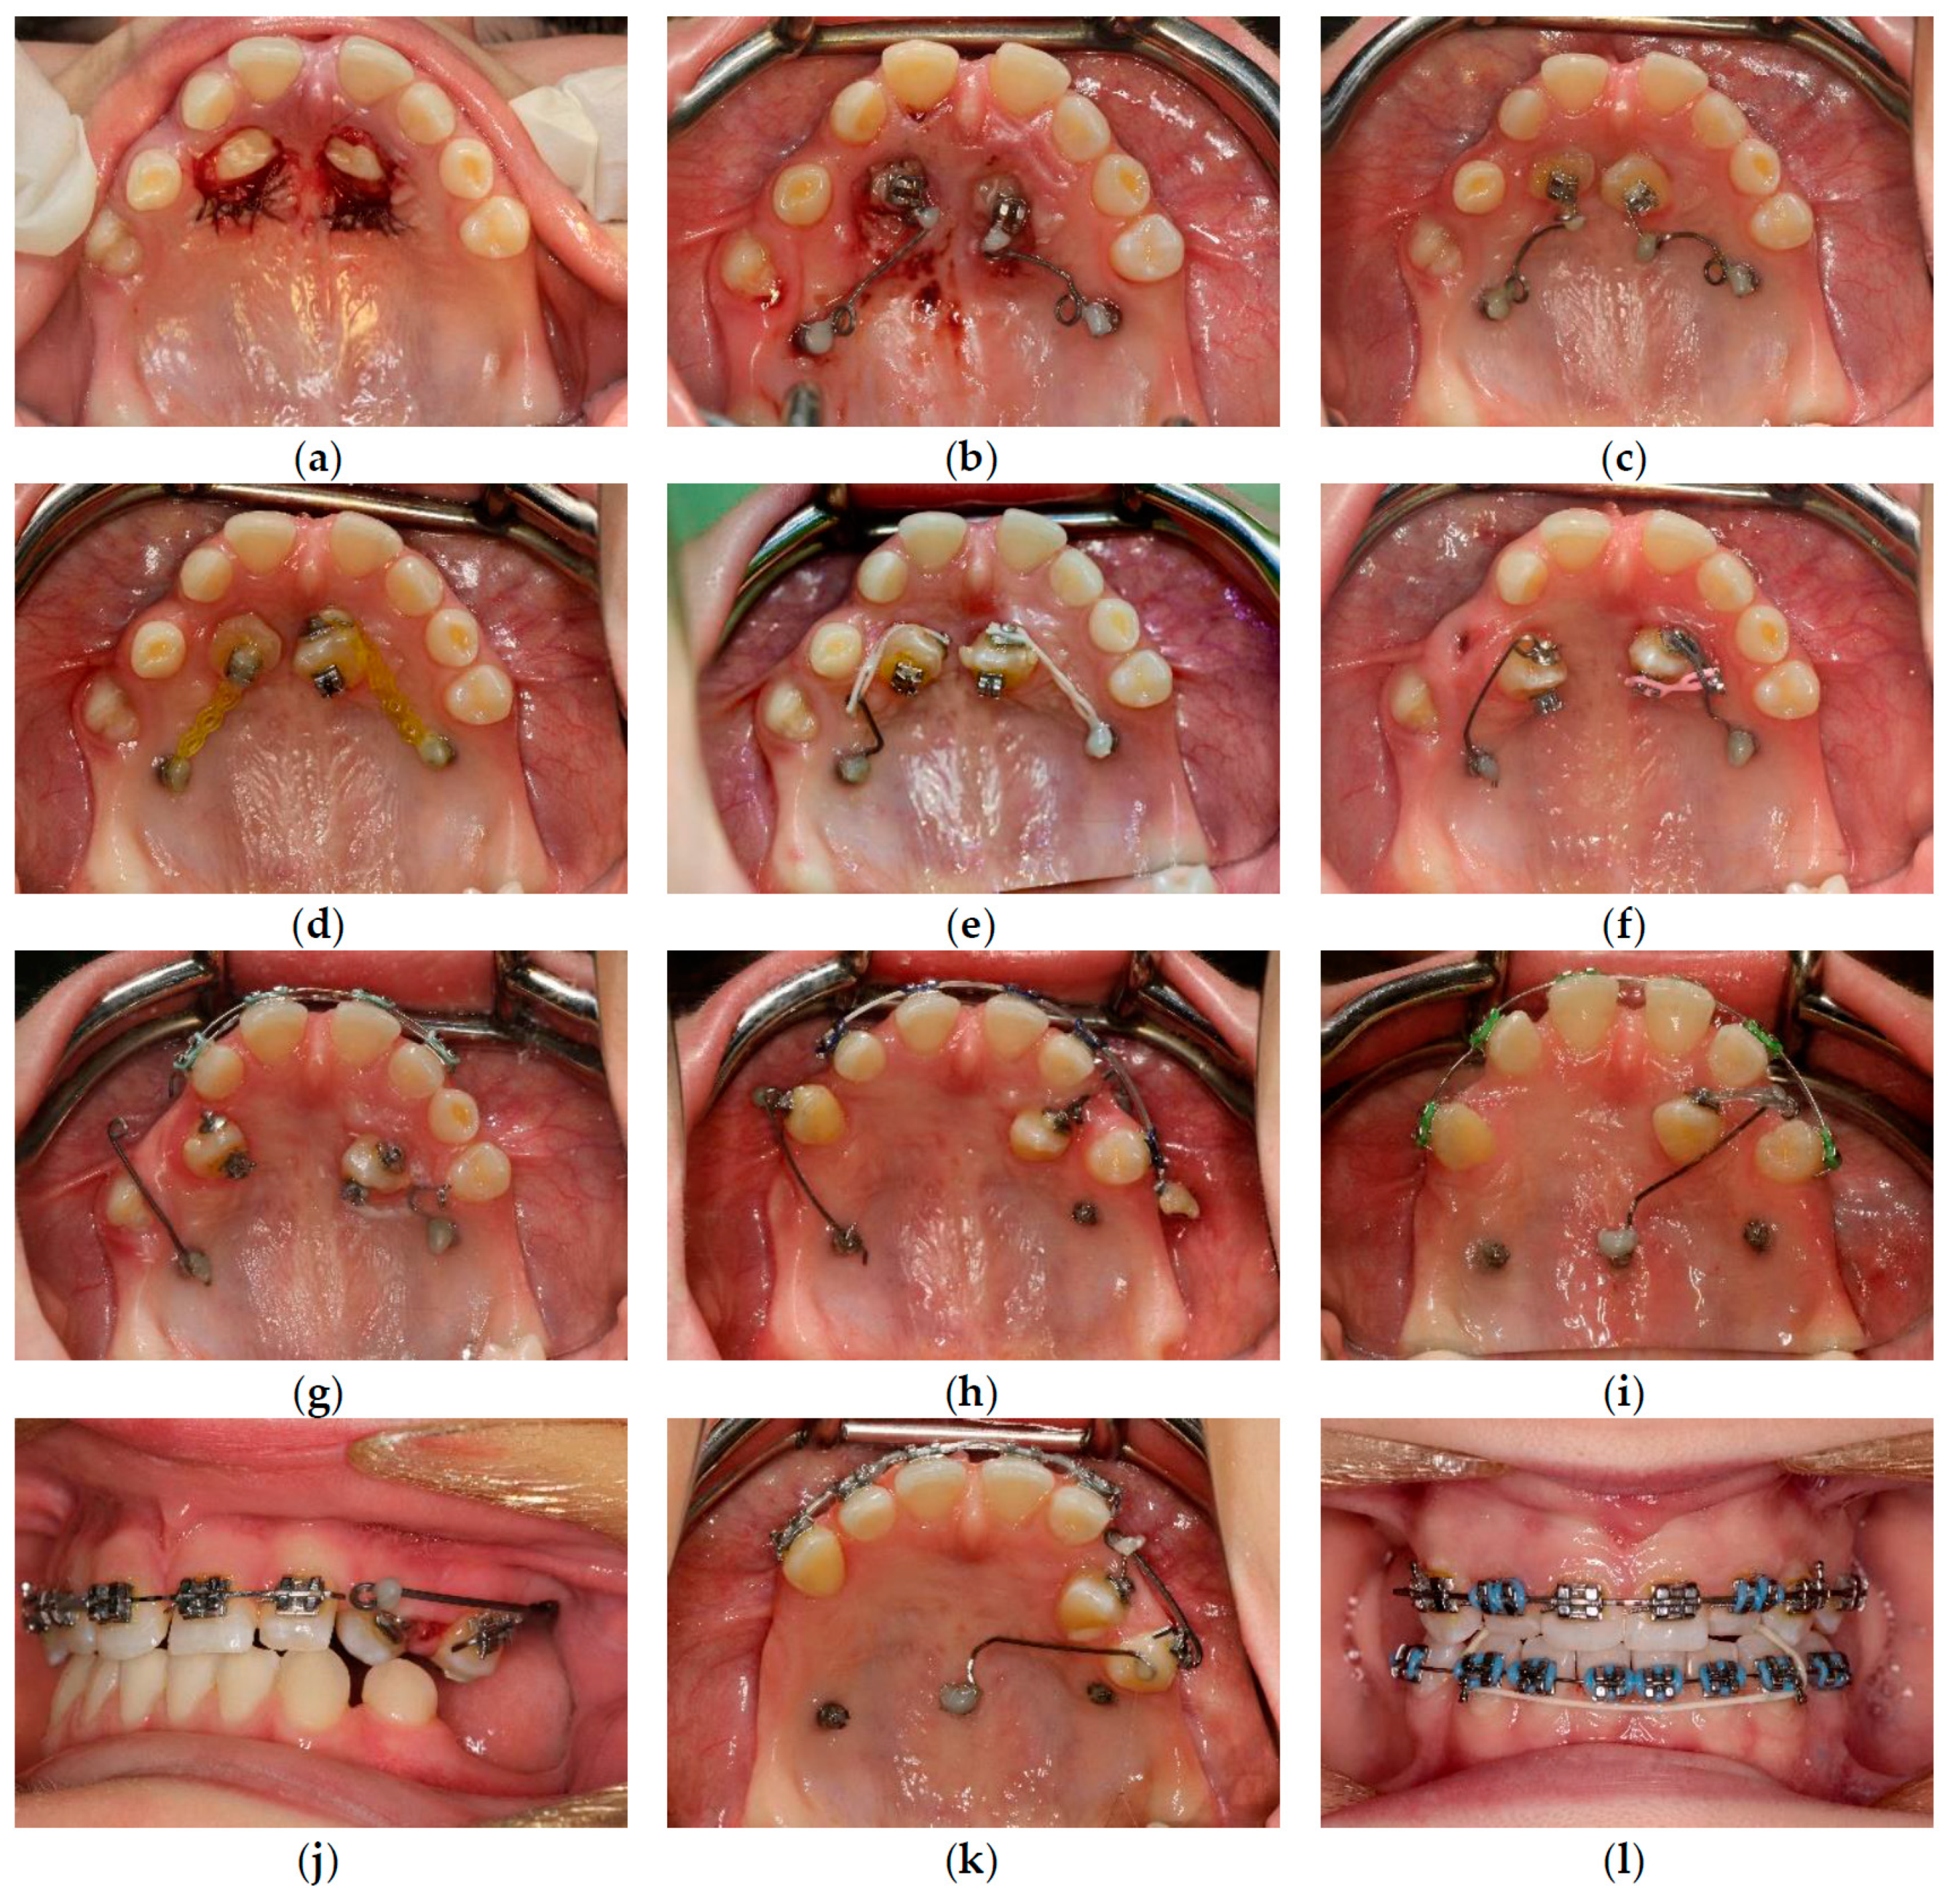

| October 2017 | PDCs’ surgical exposure—open technique; brackets bonded on PDCs; MIs tomas®-pin SD 06 (Dentaurum, Ispringen, Germany) inserted in the palatal alveolar region; 0.016″ × 0.022″ TMA cantilevers activated in distal and downward direction (50 g) (Figure 6a,b). |

| November 2017 | Visible orthodontic movement—exclusion of primary ankylosis (Figure 6c). |

| December 2017 | Increased mobility and tenderness of PDCs, dismantlement of cantilevers, button on the buccal side of UL3 (derotation), power chains to move the teeth (Figure 6d). |

| January 2018 | Teeth stability improved; 0.017″ × 0.025″ TMA cantilever with activation in downward and buccal directions for UR3, power chain for distal movement and derotation of UL3. |

| February 2018 | Button on the buccal side of UR3 (derotation), power chains for distal movements and derotations (Figure 6e). |

| April 2018 | Extraction of the upper right deciduous canine due to the collision with movement of UR3; 0.017″ × 0.025″ TMA cantilever activated for buccal movement of UR3 (50 g) (Figure 6f). |

| June 2018 | Partial fixed upper SS appliance Equilibrium® 2 0.022″ in Roth prescription (Dentaurum, Ispringen, Germany), 0.016″ NiTi wire, continuous metal ligature to create space for UL3; cantilever activation (Figure 6g). |

| August 2018 | Bracket on tooth no. 24; 0.016″ NiTi wire and open coil spring to create space for UL3; extraction of the upper left deciduous canine. |

| October 2018 | New MI tomas®-pin SD 08 (Dentaurum, Ispringen, Germany) was inserted in the buccal surface of left alveolar ridge; 0.017″ × 0.025″ TMA cantilever for buccal movement of UL3 (50 g) (Figure 6h). |

| November 2018 | Mobility of the buccal alveolar MI, the miniscrew was tightened and left to stabilize for a month; tooth no. 55 was extracted due to progressive reinclusion. |

| December 2018 | Buccal alveolar MI was lost and new MI tomas®-pin SD 10 (Dentaurum, Ispringen, Germany) was placed in the IZC; 0.017″ × 0.025″ TMA cantilever with buccal activation for UL3 (50 g). |

| February 2019 | Inflammation and submucous abscess in the IZC; MI removal; antibiotic. |

| April 2019 | New MI tomas®-pin SD 10 (Dentaurum, Ispringen, Germany) was inserted in the palatal suture and used as a direct anchorage with 0.017″ × 0.025″ SS cantilever and power chain for buccal movement of UL3 (50 g); 0.016” SS wire and bend-out for UR3 (Figure 6i). |

| May 2019 | Overcorrection of UR3 transversal relationship, 0.018″ SS wire and bend-out for tooth no. 22, new power chain from cantilever to UL3 for its buccal movement. |

| July 2019 | Tooth no. 22 in correct sagittal relationship; MI in the palatal suture used as an indirect anchorage: 0.017″ × 0.025 SS connection wire with tooth no. 24, 0.017″ × 0.025″ cantilever with buccal activation for UL3 (50g); 0.017″ × 0.025″ Cooper NiTi wire (Figure 6j,k). |

| March 2020 | The correct position of UL3; tooth no. 24 showed significant mobility; control panoramic X-ray: root resorption of tooth no. 24 (Figure 7); no possibility to conduct control visits on a regular basis due to COVID-19 pandemic—next appointment took place in November 2020. |

| November 2020 | 0.019″ × 0.025″ SS wire, torque expression, closure of spaces with power chain. |

| March 2021 | Removal of MIs, 0.021″ × 0.025″ TMA wire for torque expression in the upper arch; Fixed lower SS appliance Dentaurum Equilibrium® 2 0.022″ in Roth prescription (Dentaurum, Ispringen, Germany); 0.016″ NiTi wire; elastics 4 ½ oz. from palatal buttons on teeth no. 12 and 22 to the lower arch to correct the anterior crossbite (Figure 6l). |

| April–June 2021 | Further alignment of the lower teeth by means 0.017″ × 0.025″ NiTi, and next 0.019″ × 0.025″ SS; intermaxillary elastics 4 ½ oz and offset bends on teeth no. 12 and 22 were used to correct the anterior crossbite; elastic power chains for space closure. |

| August 2021 | Open sinus lift surgery with porcine bone-derived grafting material (The Graft™ bone substitute cancellous granules (Purgo Biologics, Seongnam, Republic of Korea) and BioCover™ resorbable collagen membrane (Purgo Biologics, Seongnam, Republic of Korea)) was performed on the right side of the maxilla. |

| March 2022 | Two dental implants were placed: tooth no. 14—Axiom® PX 3.4 × 12 mm (Anthogyr, Sallanches, France), tooth no. 15—Axiom® PX 3.4 × 10 mm (Anthogyr, Sallanches, France). |

| May–August 2022 | Finishing; control panoramic X-ray (Figure 8); 1st canine relationships and midline consistency; debonding of the brackets; fixed upper and lower retainers’ placement (0.027″ × 0.011″ 8-strand braided SS), tooth no. 24 was not fixed to the retainer due to increased mobility. |

| September 2022 | E-max (lithium desilicated ceramic) veneers on upper teeth; individual implant abutments (titanium pre-milled abutments) and implant-supported blocked crowns (zirconia veneered with porcelain using the cut-back technique) on dental implants; removable thermoformable retainer. |